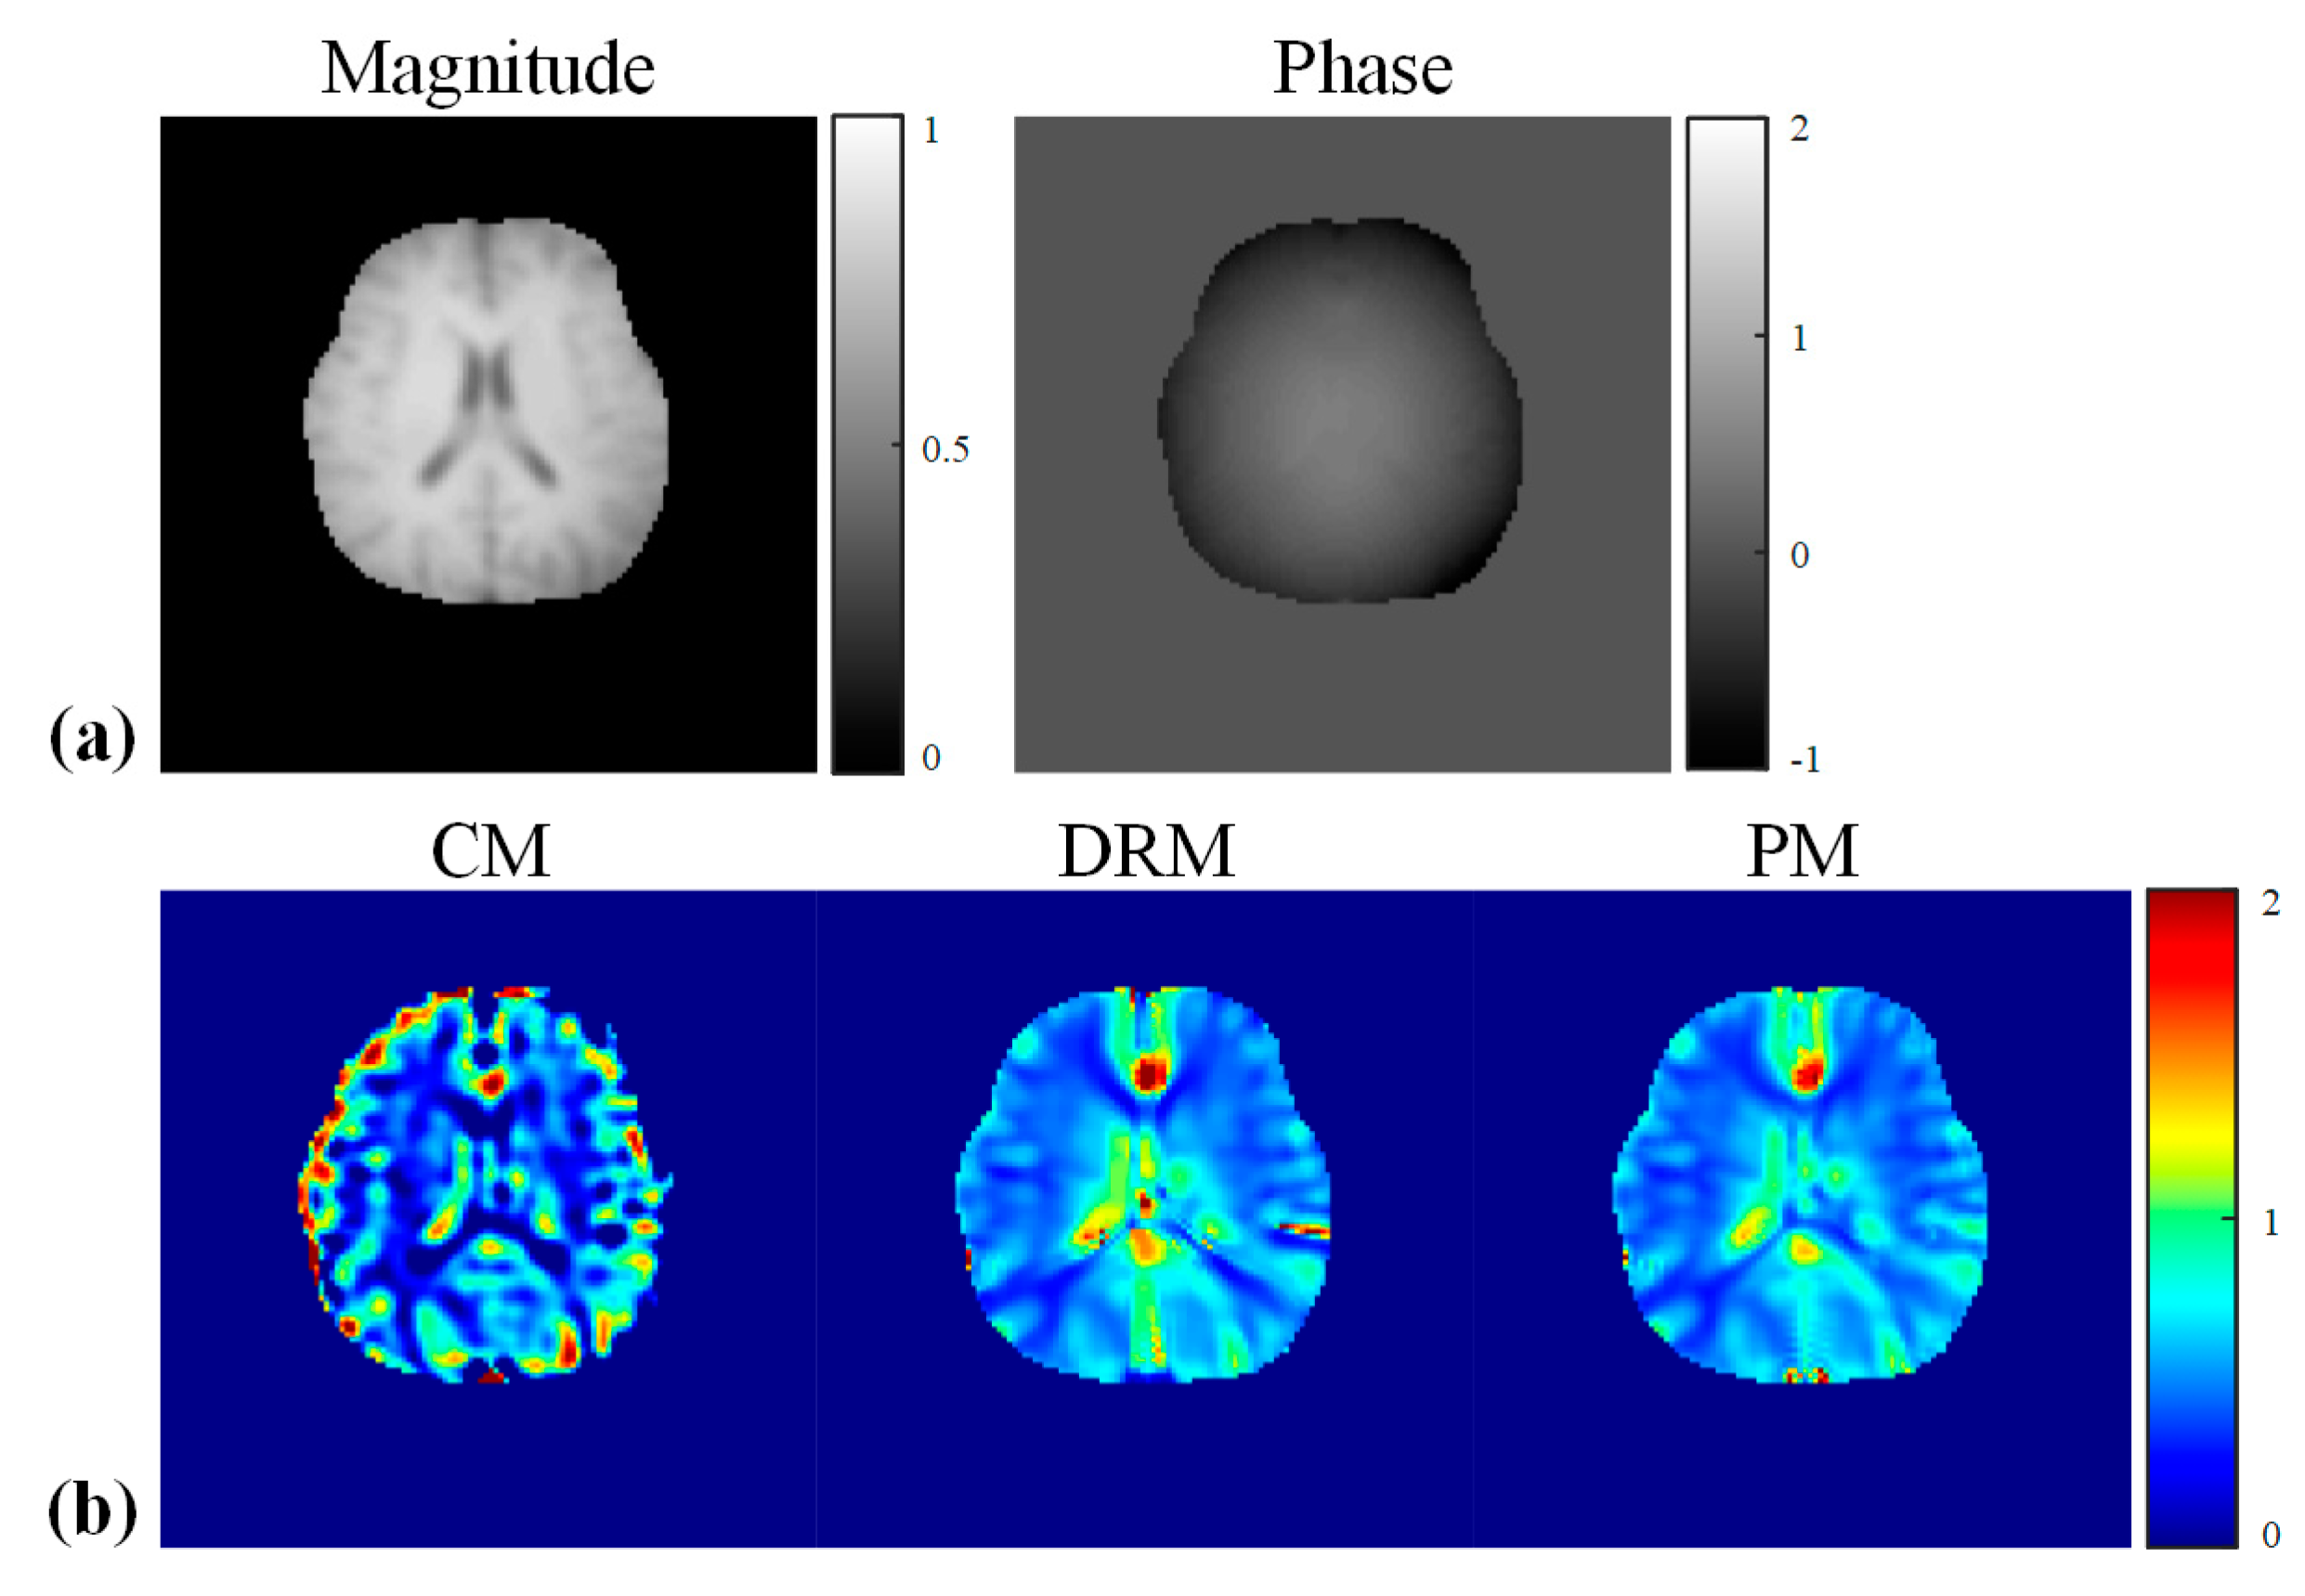

4.3. Experimental Results